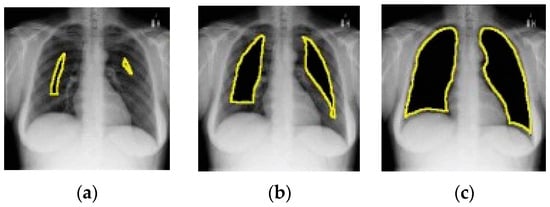

4.2. Segmentation

Like data augmentation, segmentation is a pre-processing step applied to CXR images [60]. Segmentation is typically performed to locate objects (e.g., lungs) and boundaries (e.g., lung boundaries) in images (e.g., CXR images) [61]. It enables the extraction of desired regions of interest from CXR images. Manual segmentation is tedious and time-consuming and relies on the expertise of radiologists. DL-based segmentation models have been used to obtain the lung region in CXR images. Narayanan et al. [62] have made use of CXR image segmentation as a pre-processing step. They did this using a DL-based segmentation model called U-Net [63]. Through segmentation, they were able to find out that the shape of the lung is key to differentiating between viral and bacterial pneumonia. The performance of the classification model improved as a result of incorporating segmentation in the process.

A number of DL-based segmentation models exist such as fully convolutional networks (FCNs) [64], U-Net [63], and V-Net [65]. U-Net is the most popular architecture [60]. The following are some of the studies that have exploited segmentation in CXR-based pneumonia detection: [66,67,68,69,70,71].